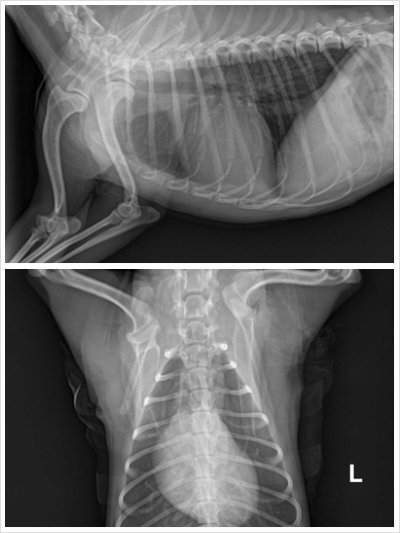

<방사선촬영사진입니다>

위에는 잘 모르겠고 아래사진 왼쪽 어깨뼈가 골절된게 보이구요

사진과같이 뼈가 부러졌는데 견갑골이 가운데부분뼈가 굵고 넓게된부분은 얇은뼈인데 얇은뼈가 으스러져 조각조각났다고 하시며 으스러진부분은 어쩔수없고 가운데 굵은뼈를 플레이트로 잘 고정시켜 수술은 잘 되었다고 하시며 이틀후에 다시 보러 오라고 하셨습니다. 마취깨는거 확인하고 체온이 돌아올때까지 기다렸다 보고 돌아가려고했는데 마취에 깨서 저를보고 안기려는 얌얌이 때문에 처치에 방해될까봐 눈물을 삼키고 동서울에서 10시 40분차를 타고 춘천으로 갔습니다.